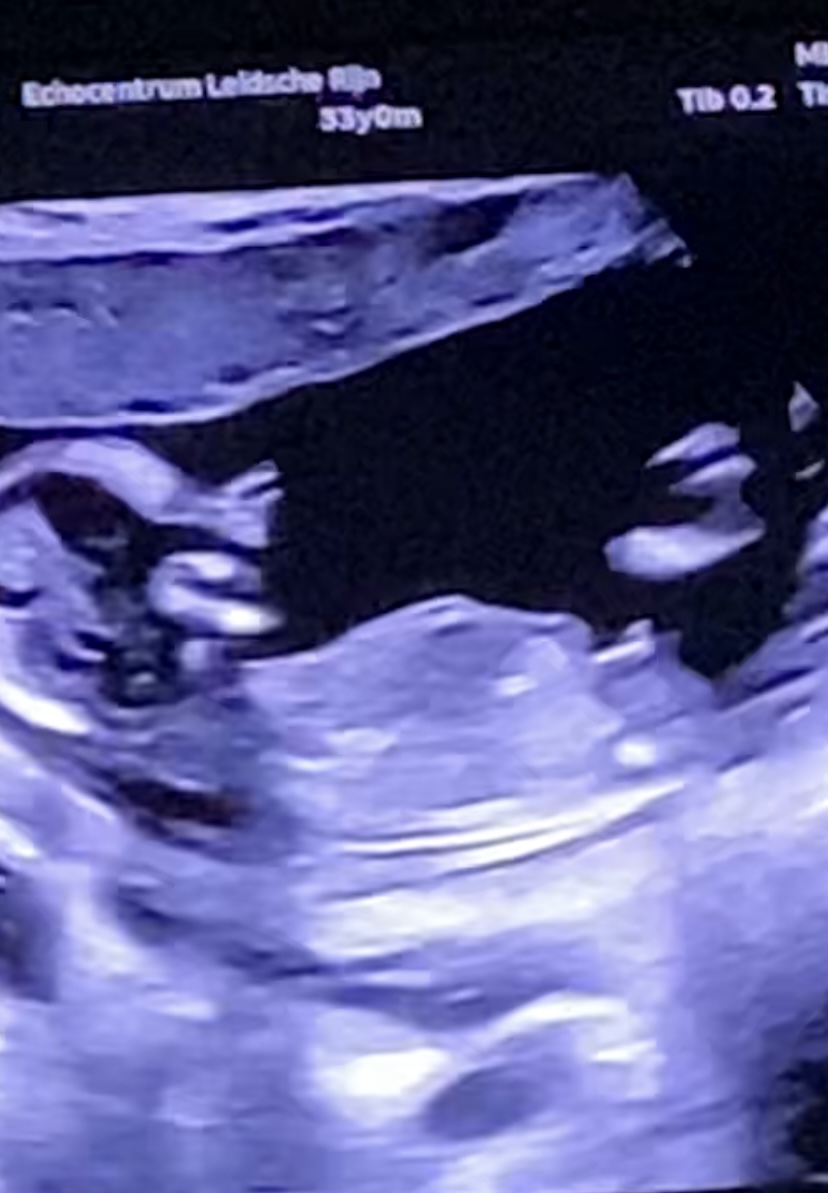

Tricky NUB 13+1 weeks? Long NUB but some stacking?

I had a scan yesterday (13+1 weeks!). During the scan I was convinced I saw long somewhat flat, but also a stacked nub (I saw a shadow in the background), but the tech said it was the stacking was the umbilical cord. The tech said she saw a flat NUB that I is why she was leaning more towards girl.

I posted my scans online and got mostly boy guesses (some girl because of the "flat" NUB) but I was wondering if it's still possible it might be a girl? That the "stacked thing" is something else??? (Already got 3 boys so a girl would be so welcome!)